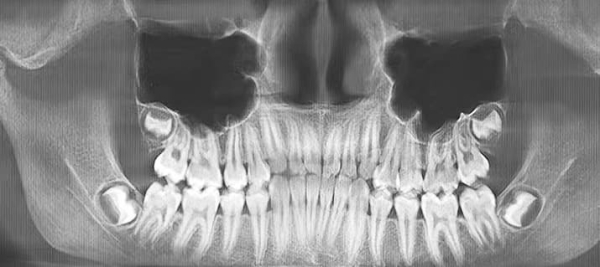

В заключение своего выступления эксперт продемонстрировал необычный клинический случай маленькой пациентки из Гродно (см. рис. 8). Родители восьмилетней девочки пришли на консультацию в Университетскую стоматологическую клинику с жалобой на то, что у нее долго не прорезываются передние зубы. Была направлена на консультацию с ортопантомограммой, что соответствует клиническим протоколам. Однако бывают случаи, когда пациентам даже в таком возрасте необходимо выполнить КЛКТ для детального анализа клинической ситуации, что и было сделано.

Рисунок 8. По результатам КЛКТ у 8-летней девочки обнаружили 8 сверхкомплектных зубов.

— По результатам ортопантомограммы было видно, что боковые резцы 1.2 и 2.2 расположены вестибулярно, а чуть прорезавшиеся 1.1 и 2.1 — сверхкомплектные, — рассказал Яков Тимчук. — После КЛКТ обнаружилось еще два сверхкомплектных в области 1.1. и 2.1. Кроме того, было еще 4 сверхкомплектных зуба в области премоляров. То есть в итоге у ребенка 8 (!) сверхкомплектных зубов. Вот насколько важно провести диагностику вовремя. Специалисты нескольких кафедр подключились к решению проблемы этой пациентки, в настоящее время ей предстоит оперативное лечение в 4-й ГДКБ.